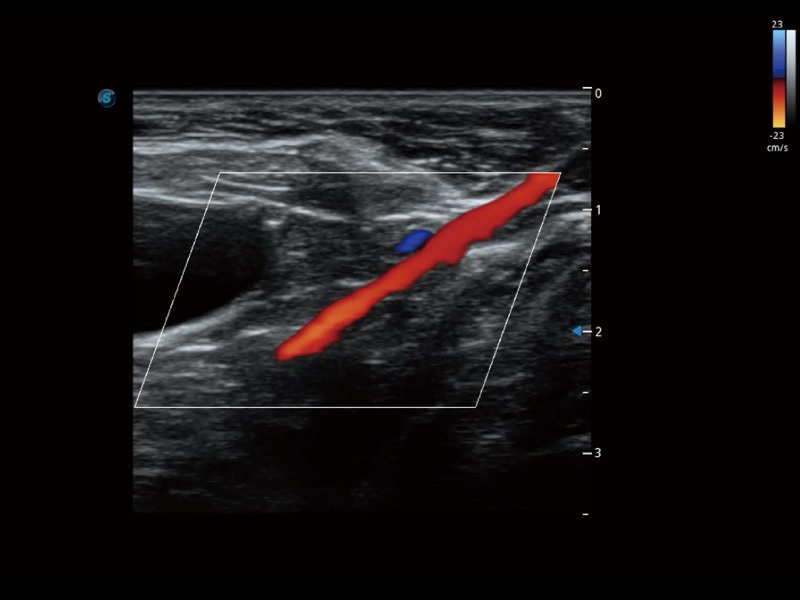

通过色彩血流和实时宽景相结合,可观察到完整的静脉或动脉的血流,方便医生检查。实时扫查过程中,如有任何操作失误也可以很容易地进行回扫擦除,而不会中断扫查。

通过创新的 Matrix E自适应滤波器和超长时间域算法,极大提升超低速微细血流的检出能力,同时更精准地滤除软组织和噪声信号,为兽用医生提供以往无法通过常规血流获得的疾病诊断信息。